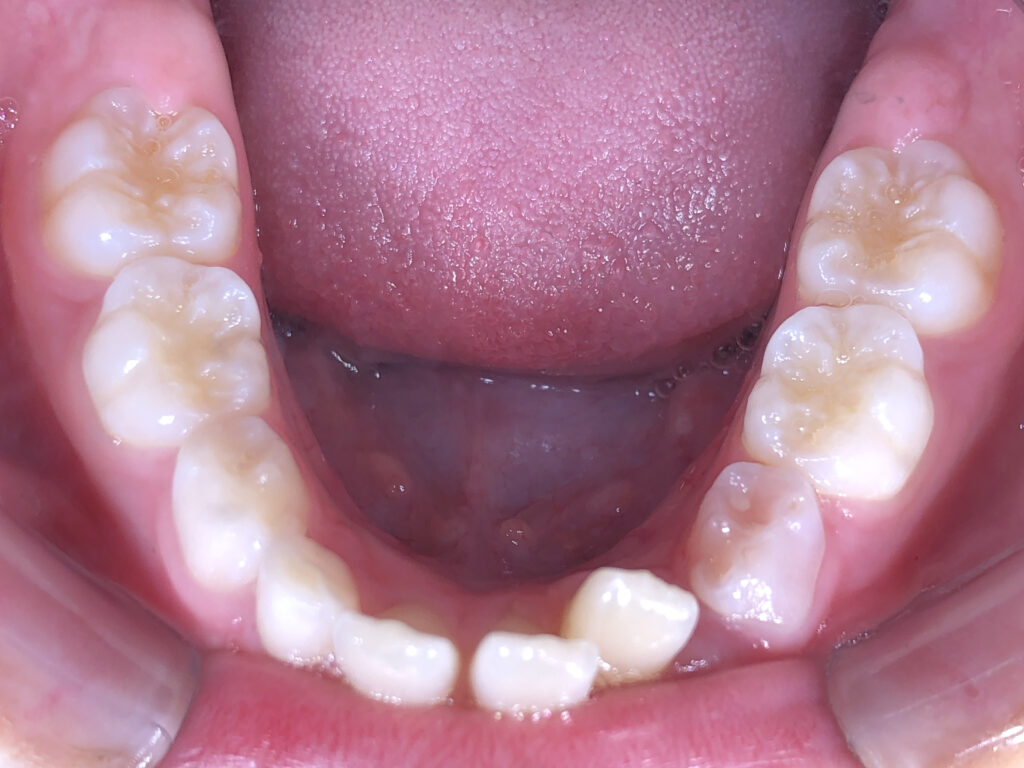

下顎

治療前